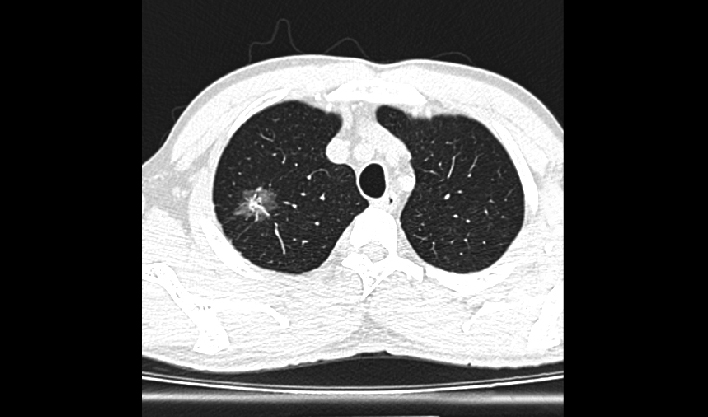

La matriz de reconstrucción de 1024*1024 amplía los datos de la imagen cuatro veces. Combinado con imágenes de corte fina, incluso las lesiones más invisibles son claramente visibles.

Captura instantánea para evitar artefactos por movimiento respiratorio, lo que mejora la tasa de éxito de los exámenes.